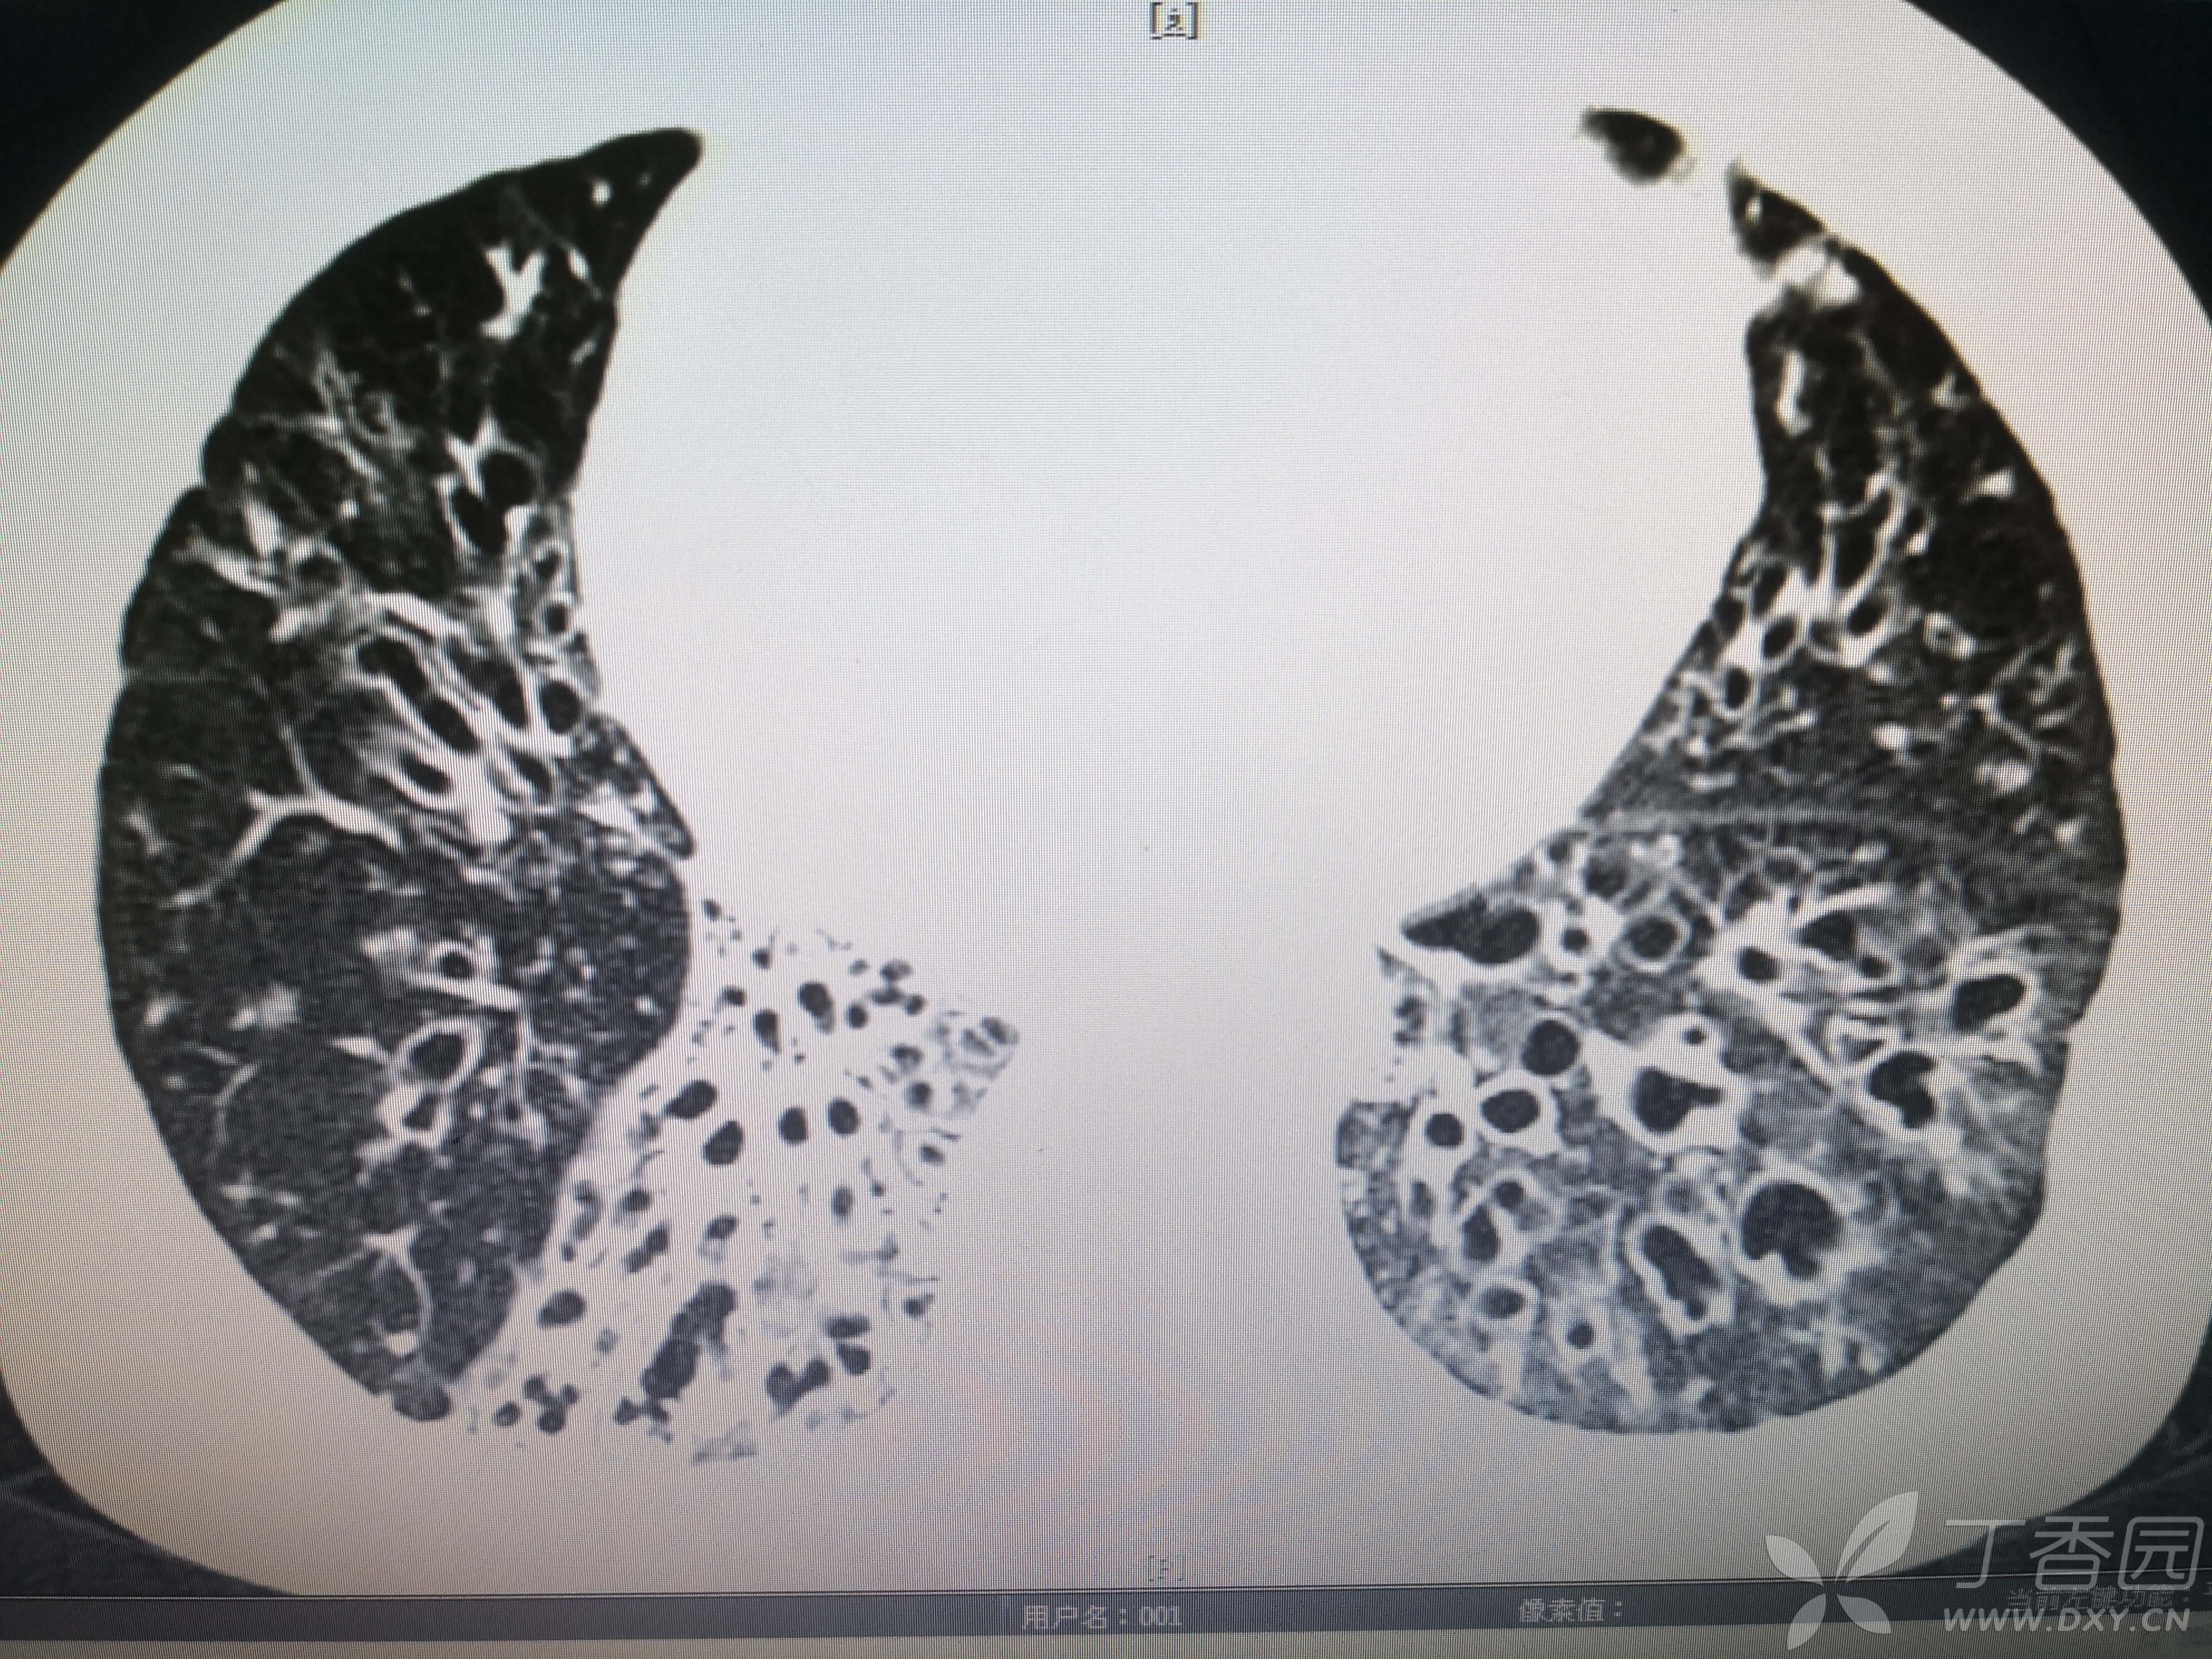

简要病史:反复咳嗽、咳脓痰40余年,气喘10年,加剧2周。

体格检查:SpO2:72%,双中下肺闻及中小湿啰音。

辅助检查:见图

临床诊断:支气管扩张并感染